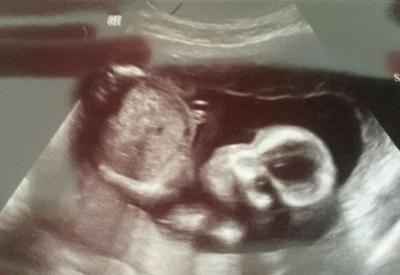

Nämlich: wo ist das Gesicht bzw. wo schaut es hin? Für mich war das bis eben selbstverständlich, bis mein mann mich auf ne andere Stelle hingewiesen hat.

Rechts ist der Kopf und links der Bauch. Das Baby schaut direkt in die "Kamera", man kann die Augenhöhlen Sehen.

Na wo Kopf und Bauch sind erkennt man schon, finde ich. Nur das Gesicht selbst... Wenn es "in die Kamera schaut", dann eher hoch oder? @sam ich glaube du siehst das gleiche Gesicht wie ich. Aber mein mann sieht noch eins ^^

Also ich seh da ganz deutlich links den Bauch und rechts das Gesicht das nach links oben schaut. Man sieht das finde ich am nasenbein!

Genau das seh ich auch. Mein mann sagte er sieht eins was runter schaut. Wenn mans einmal sieht könnte man wirklich meinen, das könnte das Gesicht sein. Da sind auch zwei Augenhöhlen und angedeutet auch nasenbein und Mund. Sieht bissl komisch aus ;)

Links der Bauch könnte man denken, dass es ein Gesicht ist weil der Bauch so rund wie der Kopf ist. Aber rechts der Kopf geht von der Kamera weg. Schaut sozusagen nach innen. Da sieht man den Bereich der Augenbrauen und die Bäckchen. Das dunkle am Kopf sind sowas wie Schatten. Das ist so meine Meinung.

Ja und in das dunkle interpretiert er ein Gesicht hinein. Er sieht es praktisch nicht, dass es hoch schaut, sondern runter. Also 2 Gesichter an einem Kopf

Rechts ist der Kopf, links der Rumpf im Bild. Es schaut leicht diagonal nach oben links. LG